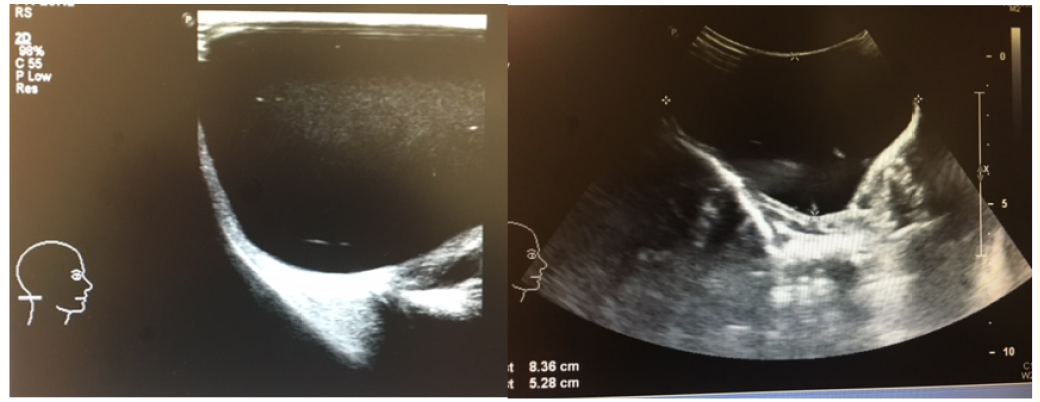

Cystic Hygroma: A Case Report in a Newborn

Jorge Sales Marques. 12(1): 24-27.